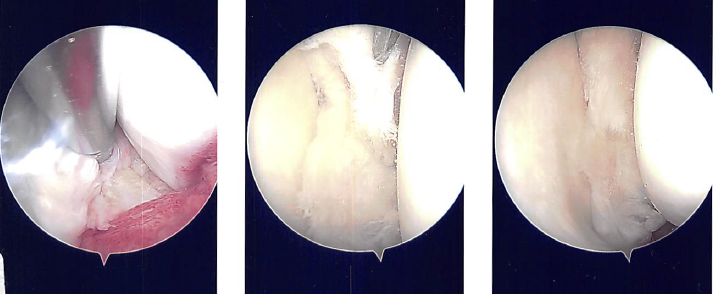

A lateral incision for the entry portal was created near the patella. The scope was given. The medial meniscus tear was visible after the scope was transferred from the patellofemoral joint to the medial compartment. The lateral compartment was examined with the scope, and it revealed fraying of the lateral meniscus and a tear in its anterior horn.

Making a medial entry portal with a spinal needle allowed for easier access to the medial and lateral compartments. A portal for entry was then created. Introduced to do the synovectomy was Shaver.

The complicated tear of the posterior horn and body of the medial meniscus was removed using upbitters and straight biters during the medial meniscectomy. Shaver was used to empty the parameniscal cyst and debride and transect margins.

The knee was discovered to be intact when the scope was advanced to the intercondylar region. The lateral compartment received the scope. The anterior horn of the lateral meniscus was torn, and the medial edge of the lateral meniscus was frayed. The meniscus was cleaned off using a razor.

There were margins of balance. Final images were captured and stored. On the medial and lateral femoral condyles, there was no arthritis. There was grade 1 to grade 2 arthritis on the lateral tibial plateau.

The scope was moved to the patellofemoral joint where no arthritis was found over the patella as well as the trochlea. Final pictures were taken and saved. The knee was thoroughly lavage.